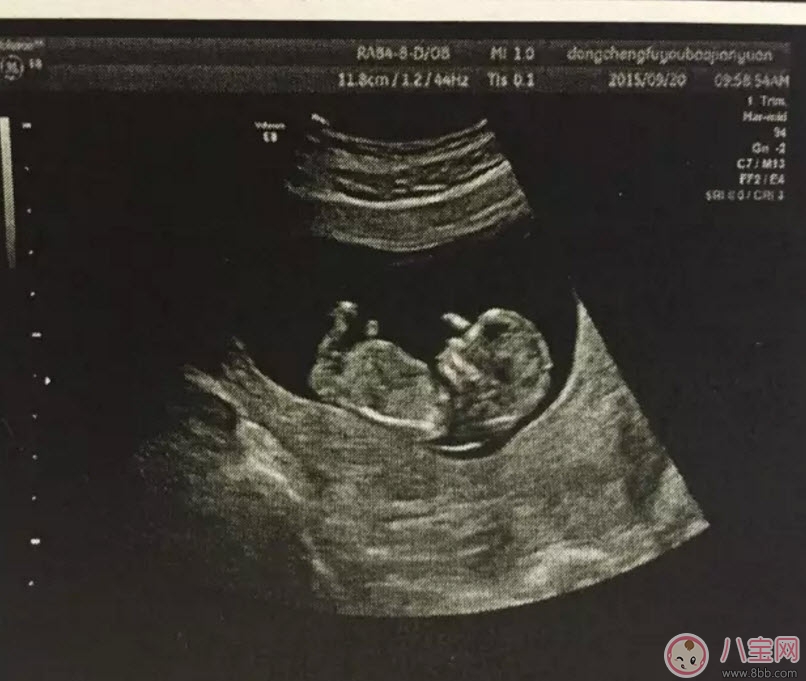

孕早期的時候用普通B超就可以了,早期只是檢測胎兒大概情況,比如檢測是否在宮內(nèi)、胎兒的頭圍、股骨長、羊水等指標。一般在懷孕8-12周做一次黑白B超確定在宮內(nèi)和胎齡。二維B超適用于孕早期。二維B超是最普通的B超,它采用的是黑白超聲診斷技術(shù),即通過超聲探頭測得的是黑白圖像,且只能觀測到胎兒的組織結(jié)構(gòu),測量出胎兒頭部、身體的長度,內(nèi)臟、骨骼的大小和形態(tài),以及是否有畸形。

通過B超能測出胎兒雙頂徑、頭圍和腹圍等數(shù)據(jù),進一步確認寶寶的預(yù)產(chǎn)期。還可幫助醫(yī)生觀察胎兒是否存活或有無畸形,羊水是否過多等。價格相對比較便宜,在90元左右(會根據(jù)各地具體情況的不同而上下浮動)。